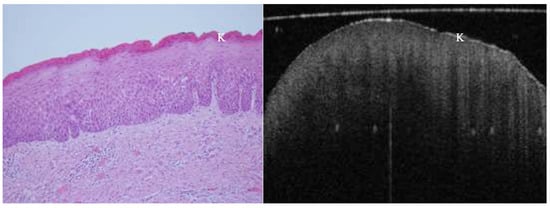

OCT performed well in discriminating dysplasia grades (Figure 1, Figure 2, Figure 3 and Figure 4). The AUC was 0.89 with an 88.0% sensitivity and 90.0% specificity for mild dysplasia. For moderate dysplasia, the highest accuracy was found: 85.0% sensitivity and 92.0% specificity yielded an AUC of 0.91. Severe dysplasia and CIS presented with lower values: the AUCs were 0.87 and 0.86, respectively (Table 4).

Figure 2. In vivo OCT and histopathology images divulge keratosis and moderate epithelial dysplasia of an erythroplakic lesion on the anterior lateral tongue.